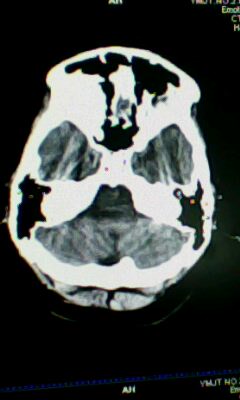

标题: CT25338:女 14岁 3岁时检查为脑积水 现在发育滞后 偶有尿失 [打印本页]

标题: CT25338:女 14岁 3岁时检查为脑积水 现在发育滞后 偶有尿失

蛛网膜囊肿!

左侧灰质异位

左侧颞枕叶区密度异常?